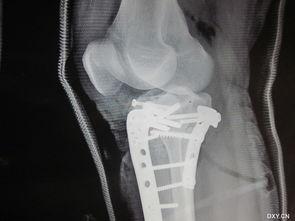

说到视觉盛宴,怎么能少得了图片呢?下面,就让我们一起来欣赏一些胫骨牵引的图片吧!

3. 牵引效果:经过一段时间的牵引治疗,患者的病情得到了明显改善。这些图片展示了患者从痛苦到康复的过程。

下面,让我们来看一个真实的胫骨牵引案例。

小王,28岁,因车祸导致右胫骨骨折。在经过一段时间的胫骨牵引治疗后,他的病情得到了明显改善。以下是他的治疗过程:

1. 入院检查:小王入院后,医生为他进行了详细的检查,确定了骨折部位和程度。

2. 制定治疗方案:根据小王的病情,医生为他制定了胫骨牵引治疗方案。